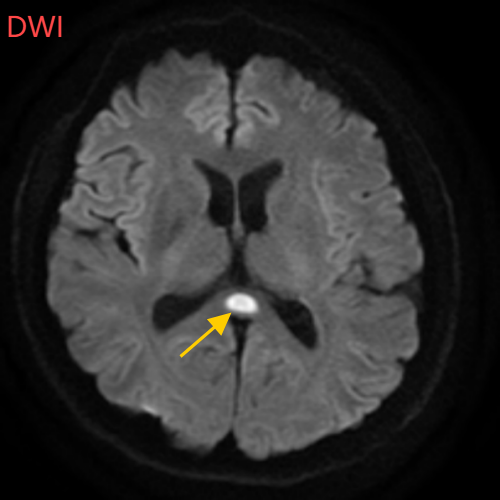

医生摇摇头,经过头部磁共振平扫、弥散、增强影像等检查,医生诊断,小董是得了一种比较少见的病症:可逆性胼胝体压部综合征。

小董的影像结果显示,胼胝体压部发生病变

经过一周治疗,小董的胼胝体压部病变明显好转